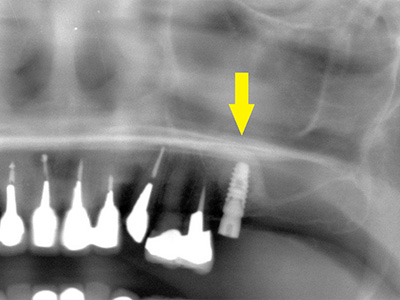

患者様は50代男性。インプラント治療前のレントゲン写真です。

右下顎大臼歯2本の抜歯後のレントゲン写真で、写真の黄色矢印は、歯の周囲の歯槽骨が大きく吸収されてしまっていました(黄色矢印)。 -